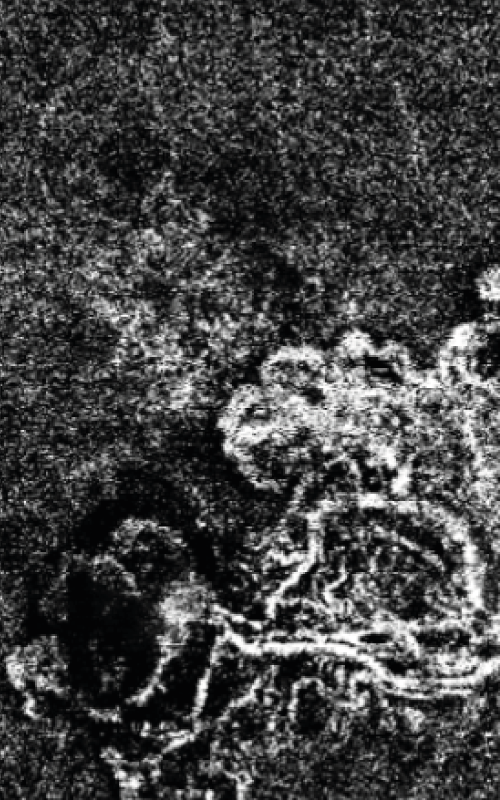

Cas Clinique – quand une CRSC se complique…

Ce cas illustre la complexité du spectre des pachychoroïdes et rappelle que toute CRSC atypique ou persistante doit faire rechercher une néovascularisation associée. L’imagerie multimodale est ici essentielle pour affiner le diagnostic et orienter la prise en charge.